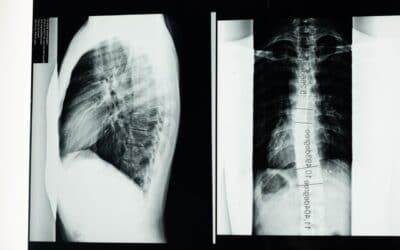

Understanding the Basics of Digital Radiography

In the past, a physical x-ray film would be exposed to the x-ray source, developed, and a metal plate exposed to the developed film. The physical x-ray film would then be developed, and the metal plate would be dipped in a solution and electroplated with metallic...